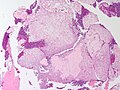

Chondromyxoid fibroma. H&E stain. | |

| LM | spindle cells or stellate cells in a myxoid or chondroid stroma, lobules with hypocellular centers and hypercellular peripheries, +/-giant cells in the hypercellular periphery, scattered calcifications, no true hyaline cartilage formation, no mitotic activity |

Features:[3]

- Spindle cells or stellate cells in a myxoid or chondroid stroma.

- Lobules with hypocellular centers and hypercellular peripheries.

- Giant cells in the hypercellular periphery.

- Scattered calcifications.

- No true hyaline cartilage formation.

- No mitotic activity.